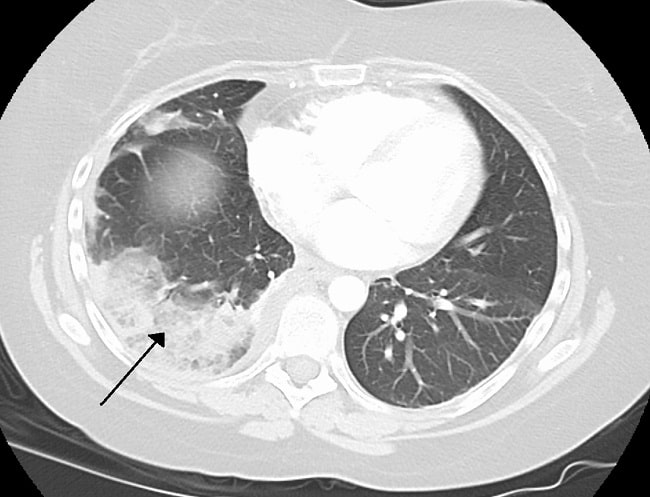

Diagnosis infark paru dapat dilakukan dengan pemeriksaan pencitraan seperti rontgen, CT scan, ataupun PET scan toraks. Dari hasil penelitian Hampton dan Castleman, 70% gambaran infark paru paling banyak ditemukan pada pasien dengan kondisi penyakit jantung kronis dan hipertensi vena pulmonal.[3,4]